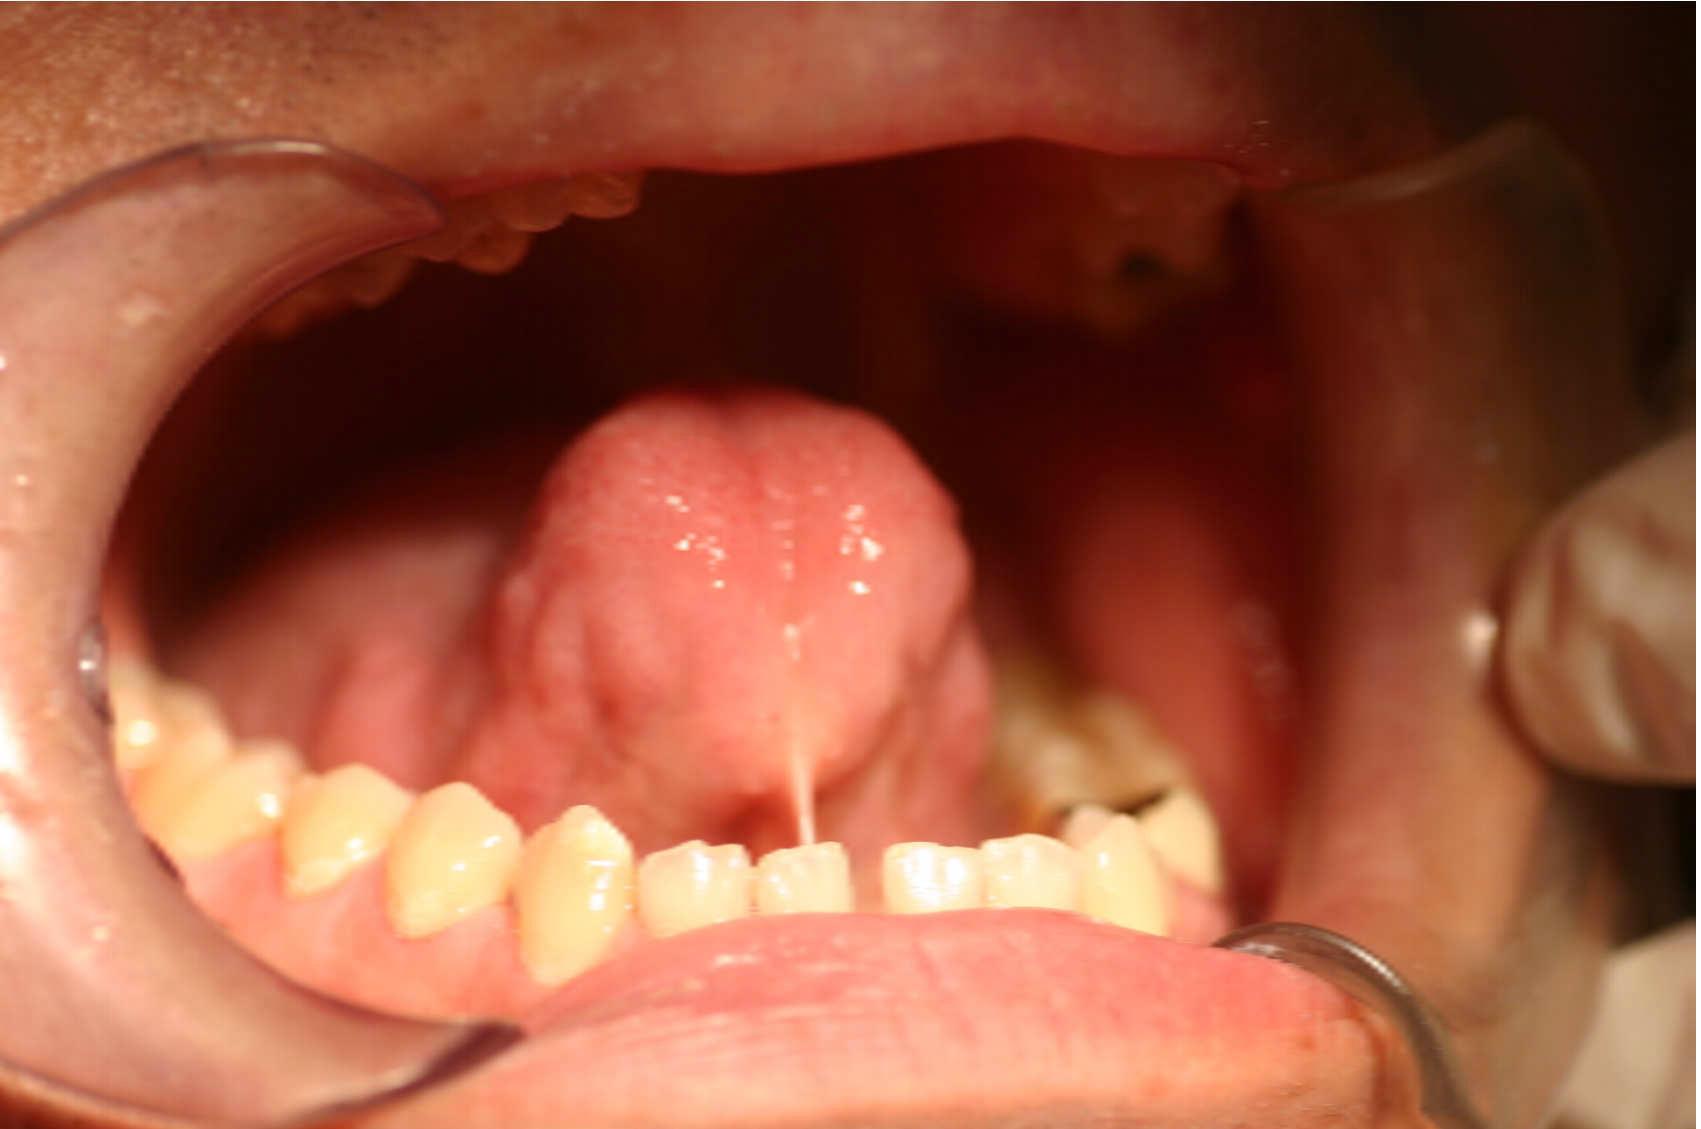

Frenotomy-Tongue

1

Prof. AnnaRita Spedicato

Laser Setting

Diode Laser 810nm

Power: 2.5 Watt,

Pulsed 50 Hz ,Fibre 400 micron